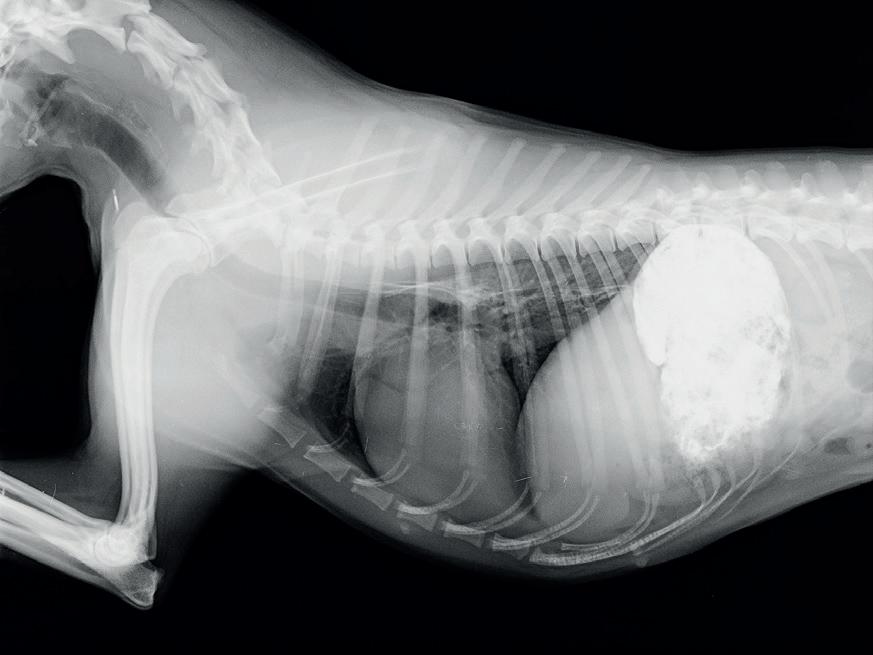

Siendo la regurgitación el principal síntoma, se realizan radiografías de la región cervical, tórax y abdomen craneal y radiografías con contraste del esófagoestomago.

Todas las radiografías de contraste se realizaron mezclando bario en polvo con agua y mezclándolo a su vez con comida húmeda, salvo en la última radiografía que se mezcló con el pienso seco que come actualmente, la comida siempre la ingirió de forma voluntaria. Se realizaron en decúbito lateral derecho y antes de 5 minutos desde la ingesta.

El esofagograma muestra una dilatación esofágica generalizada (fig. 1). El grado de dilatación esofágica se calcula mediante el Diámetro Esofágico Relativo( DER): el diámetro esofágico se mide en su punto más ancho, perpendicularmente al eje longitudinal del esófago a nivel de la superficie intraluminal (DE), relacionándolo en la misma radiografía con la medida de la entrada del tórax (ET): distancia desde el aspecto ventral de la columna vertebral en el punto medio de la primera costilla hasta el aspecto interno del manubrio esternal en el punto del diámetro más estrecho de la entrada del torax. DER=DE/ET

Siendo el DER en la primera radiografía de: 0,92.

En la radiografía del tórax no se observan cambios compatibles con neumonía por aspiración.

1A. Radiografía de contraste mostrando la dilatación esofágica generalizada

1B. Cálculo del DER sobre la figura

En la radiografía de contraste (fig. 3) aún se evidencia la dilatación esofágica con un DER de 0,68, por lo que viendo que la perra se encuentra mejor sintomáticamente y no presenta efectos secundarios achacables a la medicación se decide prolongar el tratamiento. Según la descripción de un caso clínico publicado (5),con la prolongación del tratamiento más allá de 15 días el animal siguió mejorando. Se mantuvo la alimentación en posición erguida, durante

propietarios son reticentes a retirar la medicación por lo que se reduce la dosis a la mitad. A los dos semanas del cambio la perra no ha tenido ningún episodio de regurgitación por lo que se retira la medicación y se le repite la radiografía de contraste observándose una disminución significativa del DER ( Fig.4),aún se le mantiene la alimentación en posición erguida.

Desde entonces lleva 10 meses desde que dejó la medicación y 9 desde come en posición normal y no ha presentado más episodios de disfagia o regurgitación, su condición corporal es de 5/9, se le ha realizado la ovariohisterectomía sin complicaciones y en las radiografías de control (figs. 5 y 6) no se aprecia ya dilatación esofágica y presenta un vaciado esofágico rápido y completo.